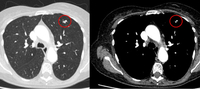

Computed tomography (CT) showing examples of malignant perifissural nodules. Note the spiculated edge of the nodules and the evident retraction of the adjacent fissure. Both resection tissue analyses confirmed adenocarcinoma of lung

From the collection of Dr George Tsaknis, MD, PhD, FRCP(London), MRQA, MAcadMEd, PGCert; used with permission